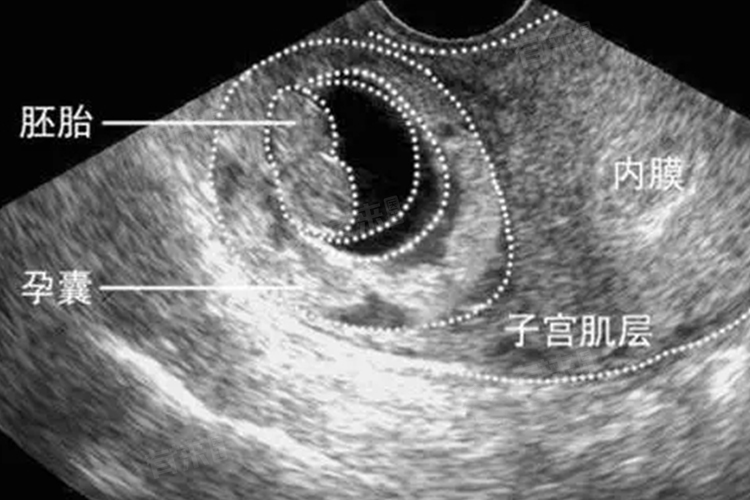

在胚胎发育过程中,心脏是最早形成并开始发挥功能的器官。胚胎在受精后的第3周左右,中胚层细胞开始分化并聚集,形成原始的心管。这一阶段,心管呈现为一条简单的管状结构,但其发育速度极快,随后迅速折叠、弯曲并分化为四个心腔,即左心房、右心房、左心室和右心室。到胚胎第4周,心脏已具备初步的循环功能,血液循环也随之启动,为胚胎的生长提供必要的营养和氧气。

- 心脏的早期形成是一个高度复杂且精密的过程,涉及多种细胞的分化、迁移以及基因的调控。研究表明,心脏的发育受到多种信号通路的严格调控,这些信号通路确保心管的正确折叠、心腔的分化以及心脏的节律性收缩。在胚胎第5周,心脏已初具形态,并开始有节律地跳动,其跳动频率远高于成人心率,以满足胚胎快速生长的代谢需求。